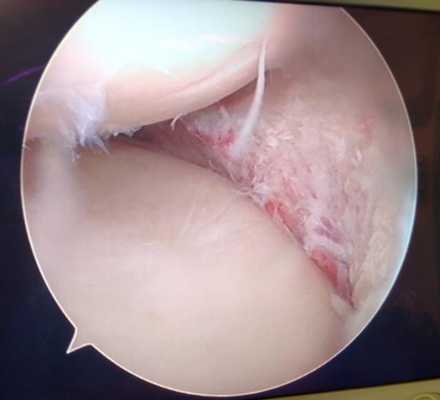

Продольные трещины на хряще большеберцовой кости после эпизода подкашивания после разрыва передней крестообразной связки коленного сустава.

Дегенеративные изменения суставного хряща коленного сустава появляющиеся на фоне повреждения разорванным мениском.

Повреждения хряща коленного сустава.